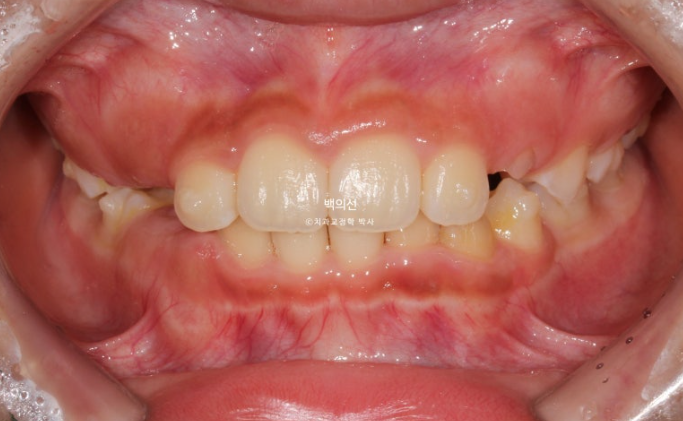

24.02

과개교합은 개선이 되어 아래앞니가 보이고 중심선은 잘 맞습니다.

앞니 뻗침과 돌출은 해결이 되었고 그 사이 남아있던 유치가 여러개 빠졌습니다.

좁았던 악궁이 넓어지면서 모양이 잡혔고

삐뚤했던 아래 앞니는 가지런해졌고 송곳니는 악궁확장을 통해 공간이 생기면서 제자리로 잘 올라오게 되었습니다.